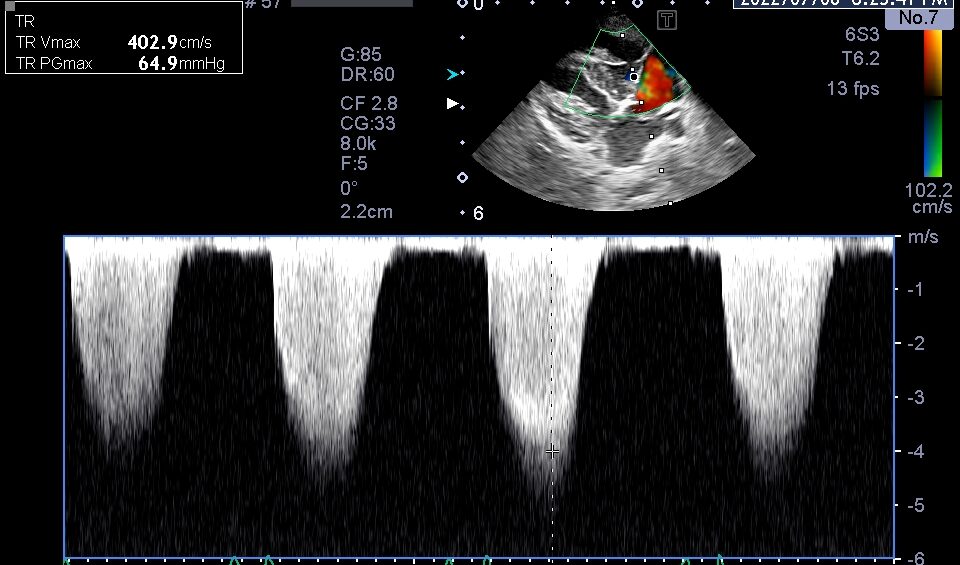

治療強化後の心臓超音波検査。右心系拡大の改善を認める。

心室中隔扁平化の改善

以前と比較して、三尖弁逆流速度の低下を認める

肺高血圧症に対する治療強化後の再診察では、上記のような心臓形態の改善を認めた他、呼吸の改善や腹水の顕著な減少を認めました。

これらの結果から、シルデナフィルの増量と利尿剤の追加が奏功したと判断し、内服薬による継続治療を行いました。